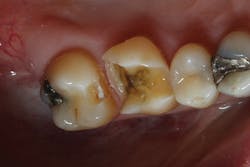

Before I began prepping for the crown, I used CariVu. On the images, I saw not only a crack on the tooth that was to be crowned, but also clear caries on the adjacent tooth (figure 6). During treatment, I snapped a picture of the preparation on tooth No. 2 with an SLR extraoral camera (figure 7). I took an additional photo midtreatment to show how far the cavity had progressed into the dentin. The bitewing didn't show any of this decay. This caries detection technology gives me a great opportunity to tell patients that I found a cavity that we would not have known about until it caused trouble. There is no surprise later and no apologies for missing an early lesion.

Figure 6: CariVu image clearly shows mesial decay on tooth No. 2.

Figure 7: Open tooth image for No. 2, confirming mesial caries.